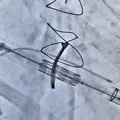

环中瓣球扩释放

环中瓣植入后左室造影